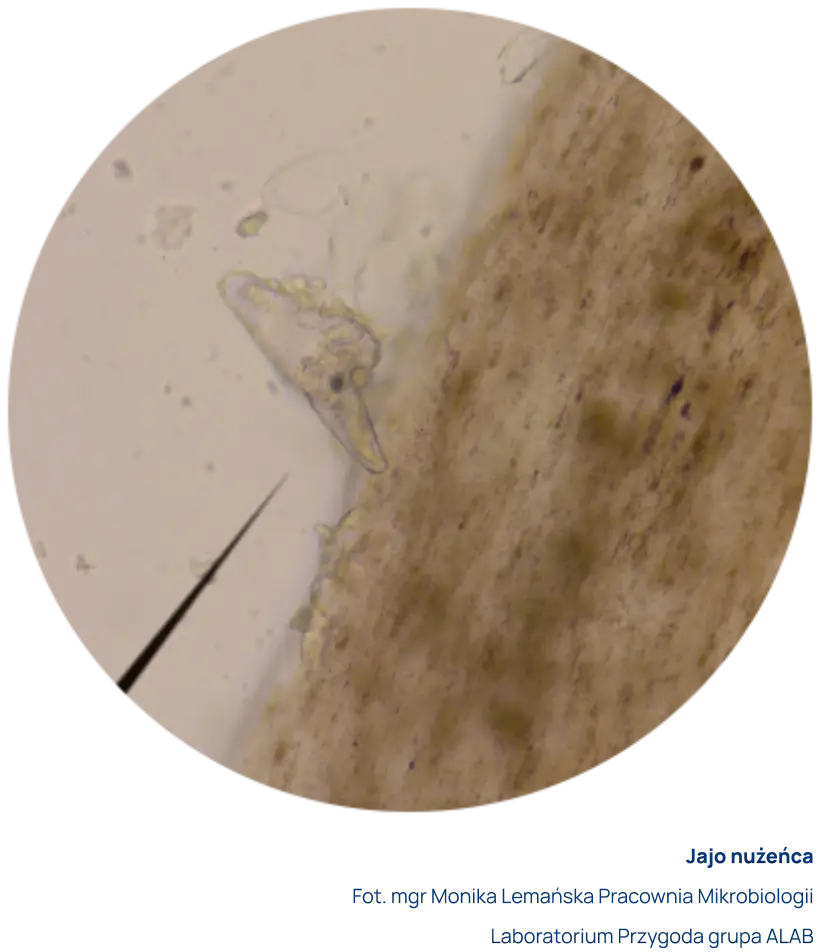

Do badania pobiera się za pomocą pincety rzęsy z obu oczu. Rzęsy umieszcza się w specjalnym płynie. Preparat mikroskopowy ogląda się bezpośrednio po pobraniu z użyciem mikroskopu świetlnego w powiększeniu x20. Dopuszczalny jest transport z Punktu Pobrań do Laboratorium w jałowym suchym pojemniku.

Za dodatni wynik uznaje się obecność w preparacie postaci dorosłych, larwalnych i/lub jaj nużeńca z jednoczesnym występowaniem objawów klinicznych